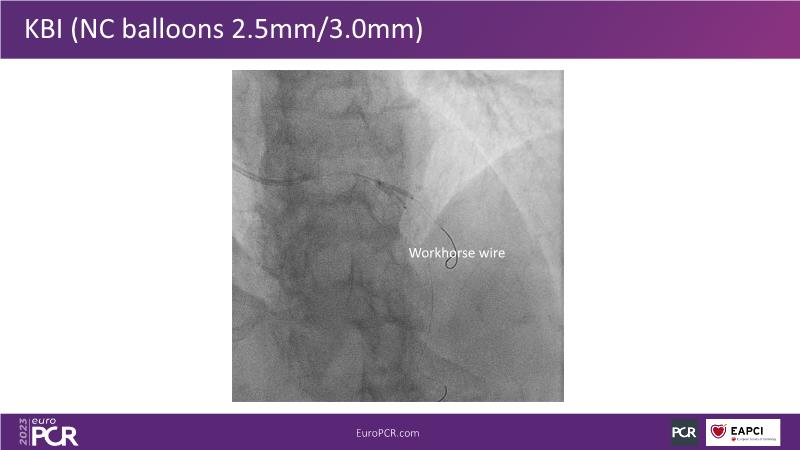

Join this session to explore the advantages of a fully optical approach in optimizing percutaneous coronary intervention (PCI) with the OptoWire III physiology wire and Nipro HF-OCT catheter. Through a practical case, you'll discover the significance of coronary physiology and intravascular imaging in bifurcation PCI and gain insights into how the performance and accuracy of the OptoWire III physiology wire can facilitate fast and reliable decision-making, particularly in side branch jailing scenarios.

- To understand how the performance and accuracy of OptoWire III physiology wire can make the difference for fast and reliable decision-making in bifurcations, particularly through side branch jailing